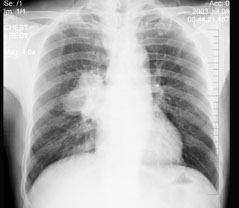

男性,59岁,痰中带血就诊,X线检查如图,最可能的诊断是 ( ) WXJ-0241.jpg

• A.肺转移瘤

• B.右肺癌

• C.结节病

• D.右肺淋巴结肿大

• E.支气管扩张